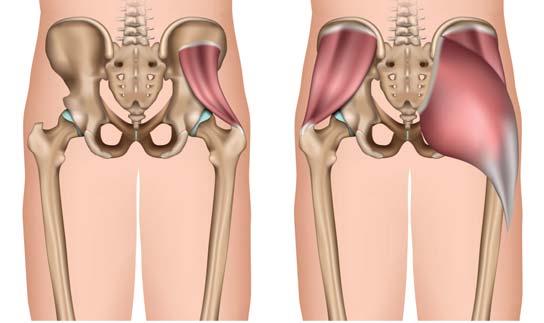

Aus medizinischer Sicht umfasst die Hüfte selbst nur das Gelenk zwischen Becken und Oberschenkel. Im Alltag verstehen wir unter Hüfte allerdings mehr. Wenn wir ärztlichen Rat wegen Hüftbeschwerden suchen, sind in 3 von 4 Fällen Weichteile im Lenden-BeckenHüft-Gürtel die Übeltäter. Es handelt sich um eine sogenannte Periarthropathie.

Schmerzende Sehnen und Schleimbeutel

Die wohl häufigste Ursache für seitliche Hüftschmerzen im Bereich des grossen Trochanters (Anatomie → S. 4) findet sich in einer Überlastung am Sehnenansatz jener Gesässmuskulatur, welche ein Einsinken nach aussen verhindert. Es liegen zuerst Mikrorisse vor.

Im Verlauf kann es aber auch zu grösseren Rupturen kommen bis hin zum seltenen Sehnenabriss. Schleimbeutelentzündungen, wie früher häufig angenommen, sind eher die Ausnahme.

Eine Sehnenentzündung ist äusserst schmerzhaft (Arthritis → S. 17). Betroffene leiden an seitlichen Hüftschmerzen beim Gehen, längeren Stehen und vor allem auch nachts beim seitlichen Draufliegen. Treten in der Leiste Schmerzen beim Beugen der Hüfte gegen Widerstand auf, ist eine Überlastung des Sehnenansatzes am kleinen Rollhügel an der Oberschenkelinnenseite wahrscheinlich.

Muskulär bedingte Schmerzen können Betroffene in der Regel genau lokalisieren. Häufig treten sie dumpf bohrend im Gesäss auf oder entlang der Oberschenkelaussenseite. Diese Muskeln führen das Bein nach hinten und aussen und lassen es nach aussen drehen. Sie sind für das Aufstehen und Gehen essentiell und damit häufige Zonen mechanischer Überlastung.